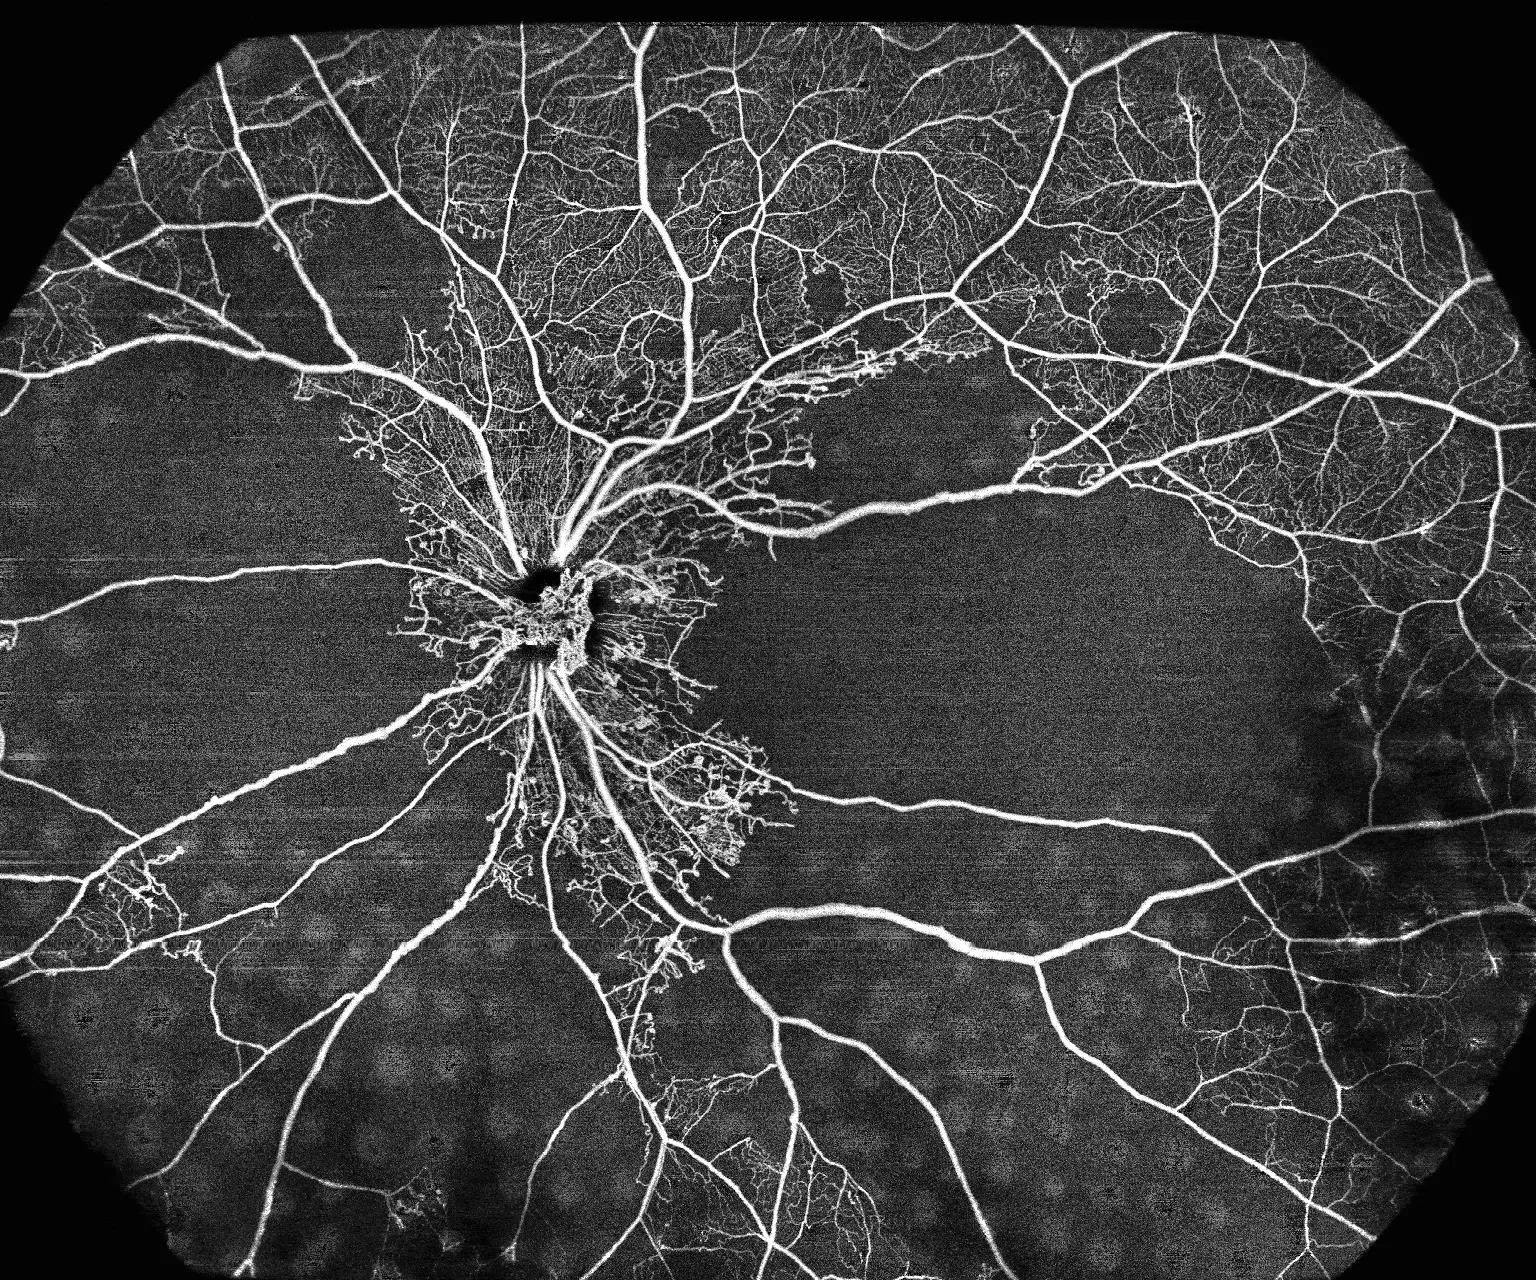

Wykrywanie wcześniej

niewidocznych patologii

Ultra-szerokokątne obrazowanie 24×20mm wykrywa zmiany obwodowe siatkówki

BMizar umożliwia diagnostykę patologii w obszarach siatkówki niedostępnych dla standardowych systemów OCT. Dzięki rekordowemu polu widzenia placówka może wykrywać wczesne stadia retinopatii cukrzycowej, obszary niedokrwienia i neowaskularyzację obwodową, co przekłada się na lepsze wyniki leczenia pacjentów i buduje reputację ośrodka jako centrum diagnostycznego najwyższej klasy.

03

Narzędzie do badań

i publikacji

10 miliardów wokseli i unikalne

algorytmy OCTA choroidy

Ultra-wysoka rozdzielczość i zaawansowane możliwości analityczne czynią BMizar idealnym narzędziem do badań naukowych i publikacji. Placówka zyskuje dostęp do unikalnych danych diagnostycznych, które mogą być podstawą publikacji w renomowanych czasopismach medycznych, współpracy z ośrodkami akademickimi i uczestnictwa w międzynarodowych projektach badawczych, budując pozycję lidera w dziedzinie.

Ultra-szerokokątne obrazowanie 24×20 mm umożliwia wykrywanie zmian obwodowych siatkówki niedostępnych dla standardowych systemów OCT